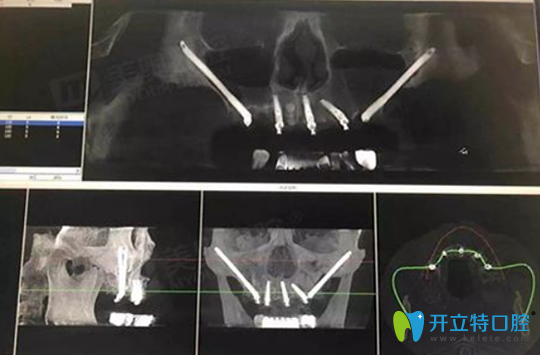

3月11日,周先生慕名來到杭州美奧口腔做全面檢查,CBCT口腔拍片顯示上頜余牙三度松動,右下頜4號牙與右下頜7號牙缺失。

患者周先生CBCT口腔影像:

患者周先生CBCT口腔影像